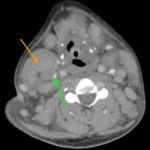

Hodgkin’s lymphoma is a neoplastic proliferation of Reed Sternberg cells and inflammatory cells within the lymphatic system. Common symptoms associated with Hodgkin’s Lymphoma include pronounced lymphadenopathy, fever, polynuclear leukocytosis, and anemia.1,2 This case study presents a unique case where an adult patient with nodular sclerosing Hodgkin’s lymphoma (NSHL) presents with rapidly progressing dyspnea due to tracheal airway narrowing. CT results showed pathological lymph nodes in bilateral cervical stations, subclavian images and within the mediastinum, concerning for lymphoproliferative disease. Otolaryngology was consulted for a possible tracheostomy; however, an awake fiberoptic intubation was suggested and subsequently performed instead. This case demonstrates the importance of immediate intervention to prevent airway loss in an atypical presentation of NSHL.